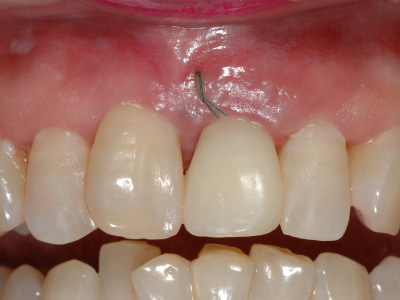

この時点では、歯と歯の間の「歯間乳頭」と呼ばれる歯茎が不足しているため隙間が空いており、インプラントの被せ物がいかにも人工物のように感じるため、審美的な仕上がりとはいえない。

そこで、上顎から切り取ってきた歯茎をインプラント周りに移植し、歯茎に厚みを持たせます。

歯茎の移植によって歯茎の隙間が埋まり、より自然な見た目を実現できました。

最終的に、周りの歯の色と形に調和するセラミックの被せ物をインプラントにセット。

歯茎との間に隙間がありませんし、色形のみでなく、すべてにおいて審美的に優れた仕上がりとなりました。